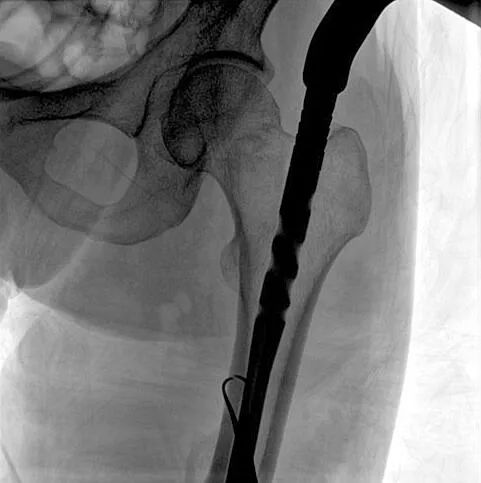

患者:男性,43歲,左股骨干骨折髓內(nèi)釘內(nèi)固定術(shù)

術(shù)中使用普愛(ài)醫(yī)療大平板一體式C形臂進(jìn)行透視,判斷骨折情況及克氏針、髓內(nèi)釘?shù)冉饘僦踩胛锏奈恢?,進(jìn)行調(diào)整。C形臂準(zhǔn)確的術(shù)中定位,大大縮短了手術(shù)的時(shí)間,減輕了患者的痛苦,輔助手術(shù)順利完成。

在進(jìn)行髓內(nèi)釘內(nèi)固定術(shù)時(shí),醫(yī)生需要同時(shí)觀察到入釘點(diǎn)和骨折部位的情況,普愛(ài)醫(yī)療大平板一體式C形臂采用30CM×30CM的平板探測(cè)器,能夠呈現(xiàn)更廣闊的成像面積,滿足大部分長(zhǎng)骨髓內(nèi)釘內(nèi)固定術(shù)的攝片需求。

術(shù)中定位準(zhǔn)確、出血量少,術(shù)后影像顯示股骨移位糾正,恢復(fù)良好力線,手術(shù)效果良好。